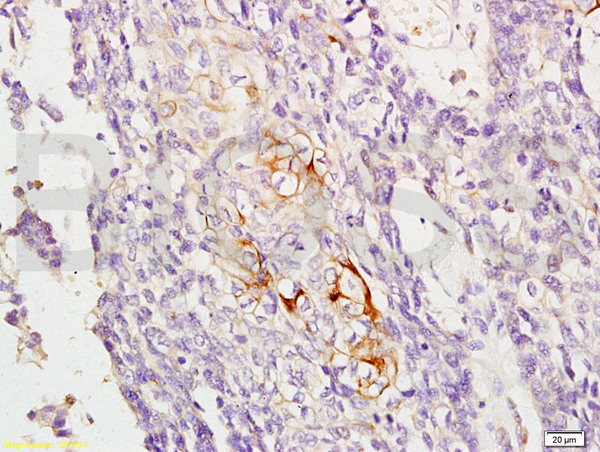

- Main image

- Experimental details

- Formalin-fixed and paraffin embedded human esophageal carcinoma labeled with Anti-RAB8 Polyclonal Antibody, Unconjugated (bs-6176R) at 1:200, followed by conjugation to the secondary antibody and DAB staining

- Sample type

- Human

- Other comments

- Esophagus